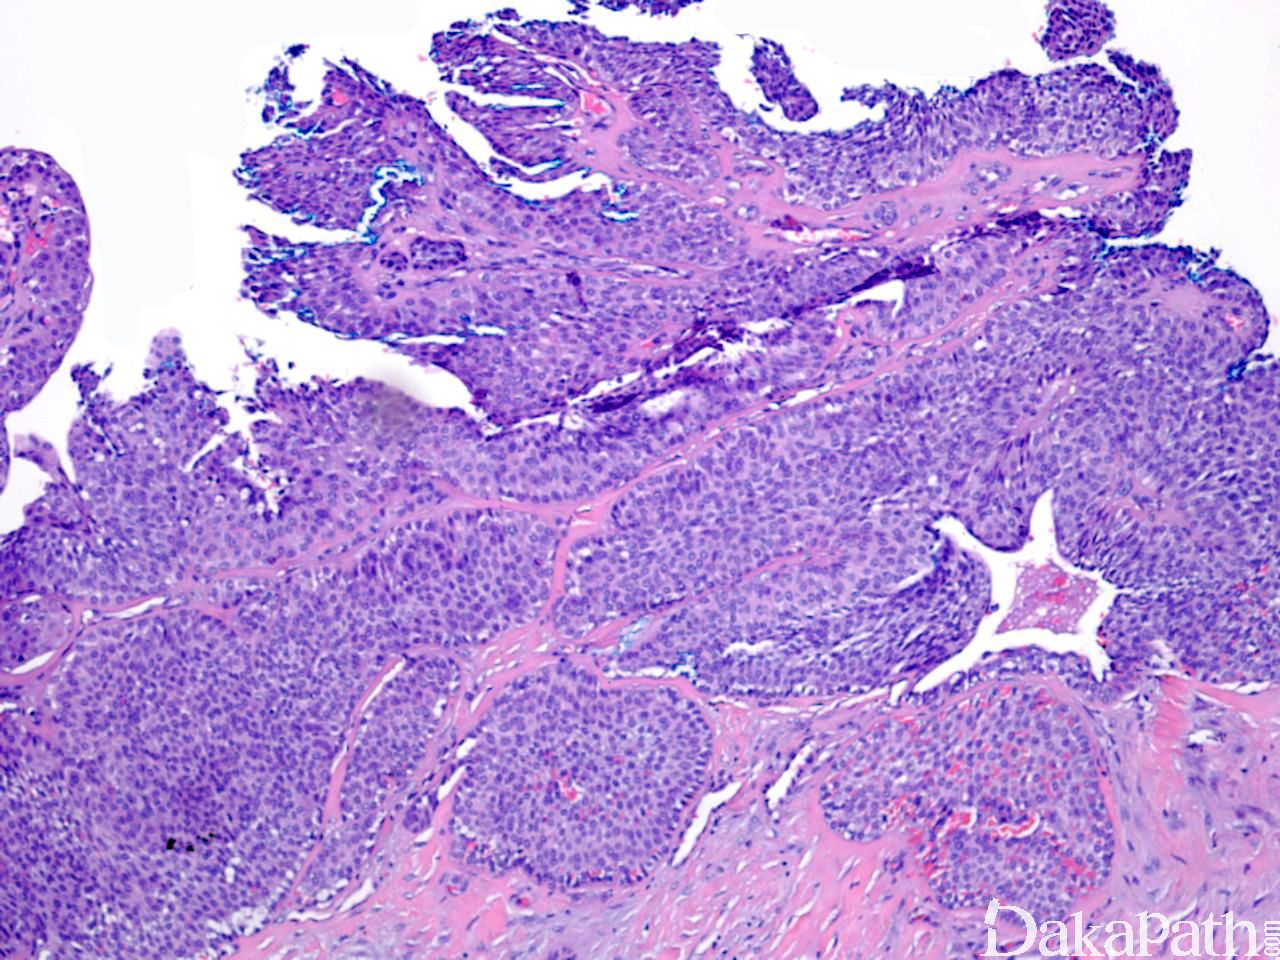

镜下见一致的嗜酸性细胞或糖原丰富透亮大汗腺样细胞增生,形成巢状或小叶状结构;

整个病变均可见到导管结构,一些导管扩张形成囊性区域,囊内充满粉染分泌物;

导管和囊性结构内衬立方形导管细胞或柱状分泌细胞,核形规则,染色质轻度增多,核分裂象少见;